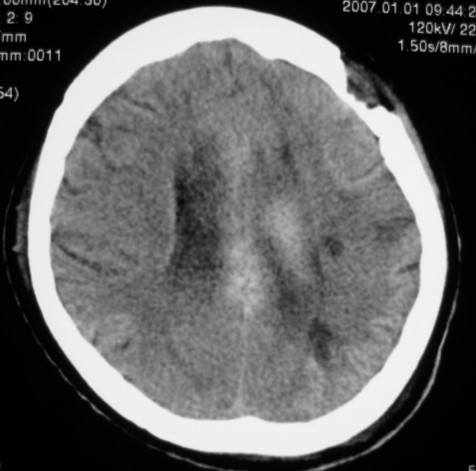

第一次ct片脑出血术后,出血吸收期。第二次ct 片左颞顶枕部及右颞顶部有脑回样高密度影。考虑珠网膜下腔出血。脑出血术后改变,脑出血恢复期 并脑积水。

第一次ct片脑出血术后,出血吸收期。第二次ct 片左颞顶枕部及右颞顶部有脑回样高密度影。考虑珠网膜下腔出血。脑出血术后改变,脑出血恢复期 并脑积水

是蛛网膜下腔出血么?蛛网膜下腔出血应该在脑沟里,而此高密度影是沿脑回分布,应该是脑膜感染后钙化灶形成。

应该是脑回钙化,不是出血

脑回状高密度影,首先要考虑脑颜面血管瘤病,不知高密度区ct值多少,对于鉴别是蛛网膜下腔出血还是钙化有意义,只是病人半月前“钙化”还较局限,因此还是考虑与脑出血有关。当然要密切结合病史及临床,增强扫描有意义。

考虑是脑回钙化,不是出血,什末样的蛛网膜下腔出血是这样的?我没见过!考虑脑炎性钙化,要结合病史!